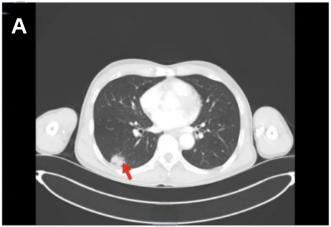

颈部、胸部、腹部增强CT:右肺下叶占位较前缩小,现约25mm×22mm(图4A);左腋窝淋巴结较前缩小(图4B)。

头颅增强MRI及DWI:左侧额叶原有病灶较前增大(图4C),左侧颞枕叶交界区见新发病灶(图4D)。

图4 右肺病灶、左侧腋窝淋巴结及颅脑病灶复查结果(红色箭头指向病灶)[1]